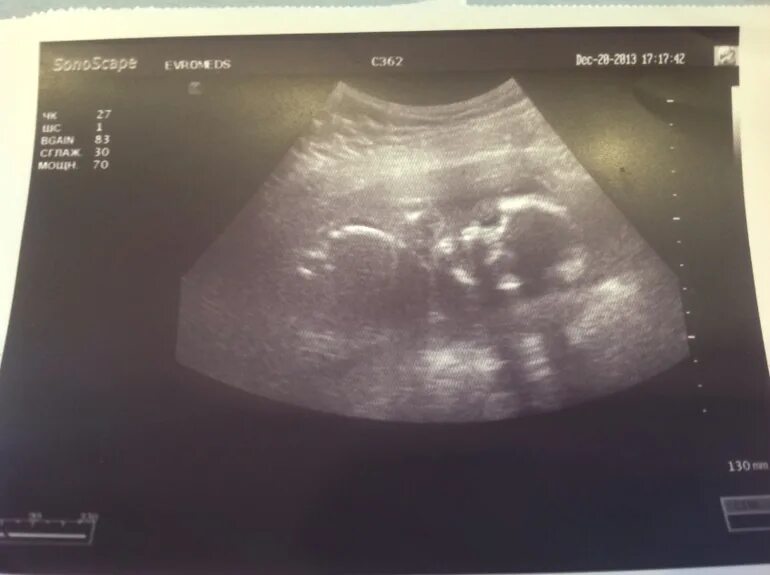

Узи 6 месяцев